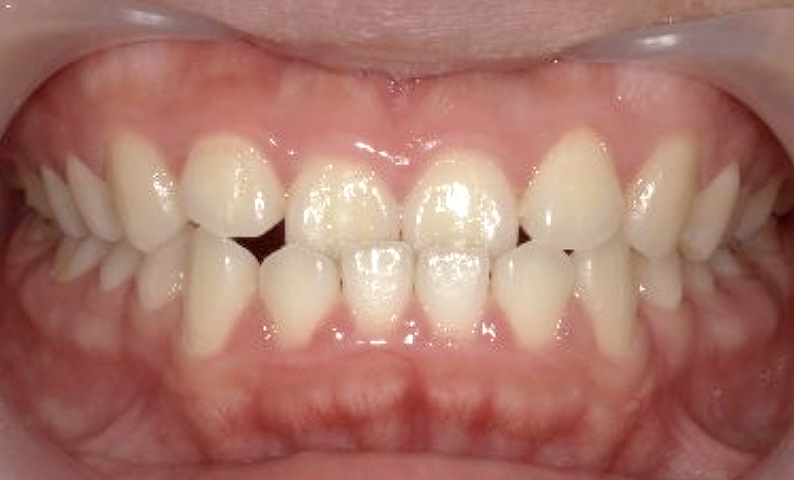

症例_018 上顎だけの部分矯正

治療期間:7ヶ月金額:30万円+税女性前歯のガタガタ上の前歯だけ

| Before | After |

|---|---|

|